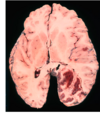

Which the following is SAH and which is ICH?

L: SAH R: ICH